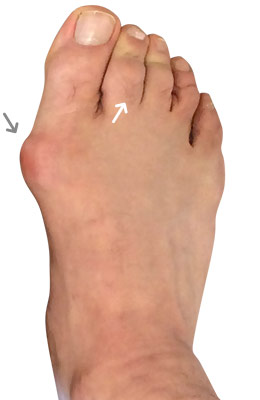

Minimally Invasive Bunion Surgery featuring the miniBunon™ System and Tailors Bunionectomy

Melissa is a 32-year-old businesswoman who could not be off her foot post-surgery, yet she had a severely painful bunion. We performed our miniBunon™ System (our trademarked minimally invasive bunion surgery) and had a dramatic correction with no downtime. Melissa continued to work after her bunion surgery and was back in shoes and full activity at 5 weeks. Melissa could not believe the results of her Bunionectomy resulting in no bony bump, no scar and amazing motion. “After” picture taken immediately following surgery. Note the bunion and bunionette (Tailor’s bunion) in the before picture.